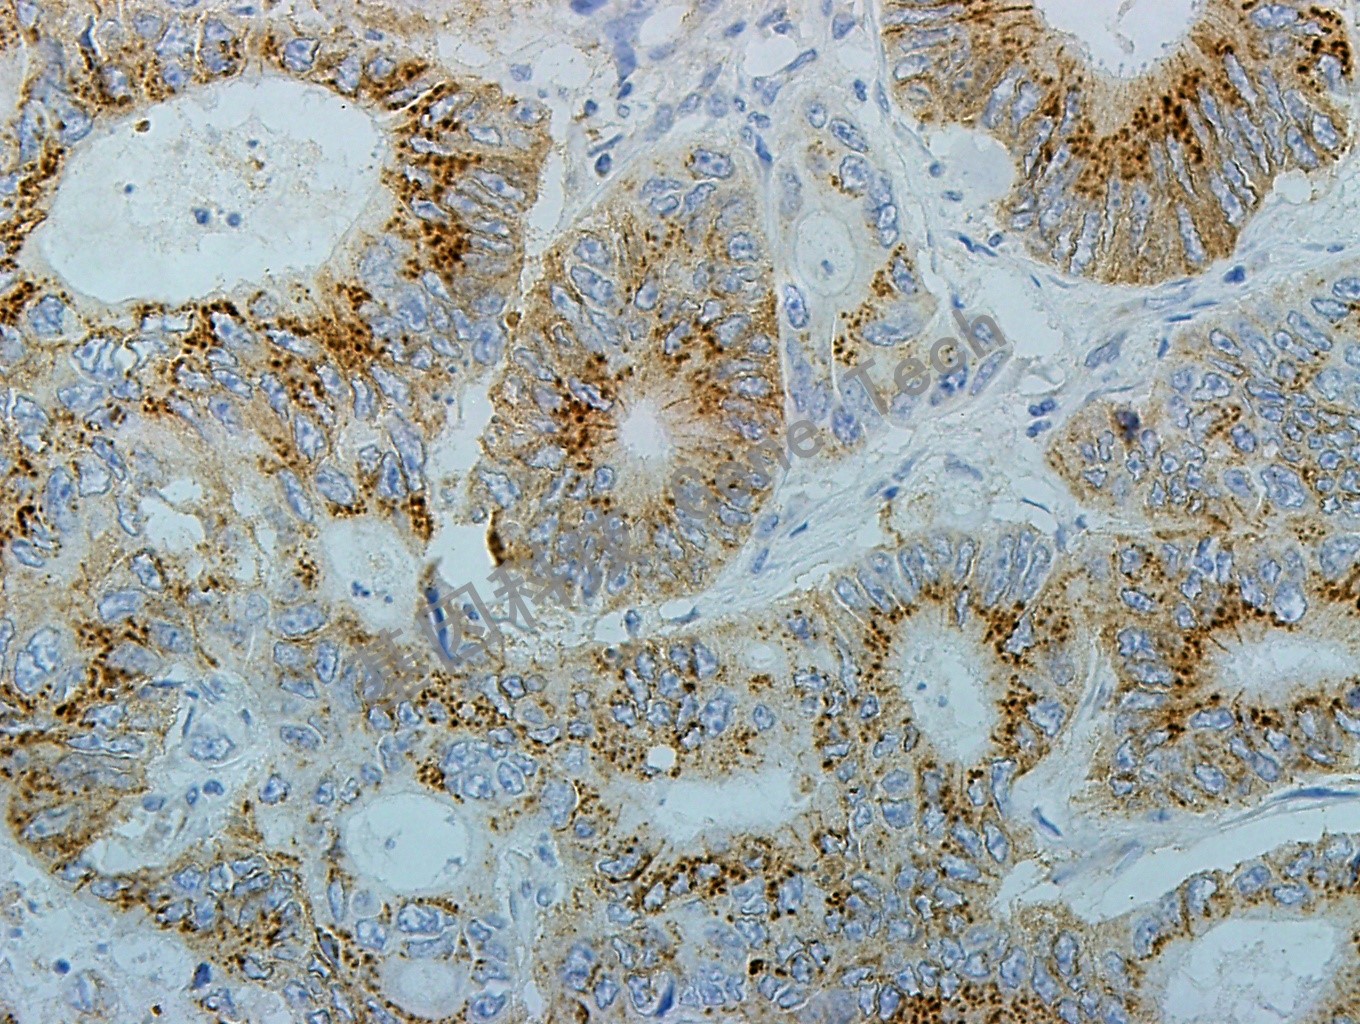

| 簡(jiǎn)介:Bak又稱Bcl-2-同源性抑制物,由211個(gè)氨基酸組成,是Bcl-2家族的同源蛋白參與凋亡控制。Bcl-2相關(guān)蛋白通過形成同源或異源二聚體形式相互作用,細(xì)胞對(duì)凋亡刺激的敏感性被認(rèn)為與這些Bcl-2家族蛋白之間的相對(duì)比例有關(guān)系。研究發(fā)現(xiàn)Bak能夠加速被剝奪生長(zhǎng)因子的粘膜下淋巴、神經(jīng)元及成纖維細(xì)胞系的凋亡。免疫組織化學(xué)染色顯示該蛋白位于胞漿內(nèi)呈斑點(diǎn)狀分布,其分布特點(diǎn)與Bcl-2家族其它蛋白一致,與其分布在胞內(nèi)的細(xì)胞器有關(guān)。 | ||

| 結(jié)腸癌石蠟切片,用 Bak(GT2229)染色,細(xì)胞漿陽性,DAB 顯色。(40×) | ||